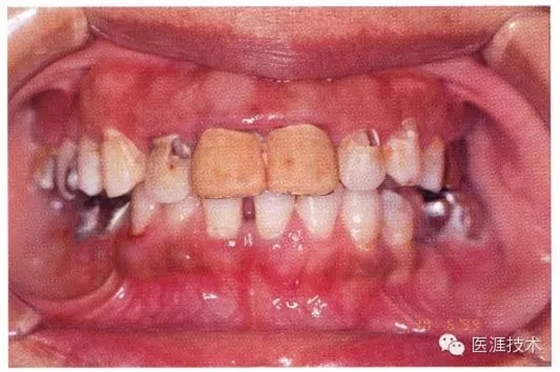

44歲牙周炎女性的臨床照片

44歲患有糖尿病病史(未治愈)。菌斑控制不良。通過牙周探診,全頜有4~8mm的牙周袋,在X光片中可以看到上頜前牙處中度牙槽骨吸收,磨牙處重度牙槽骨吸收。二次齲齒和根面齲齒也有發(fā)生。可以看到浮腫性腫脹,收到刺激后會出血。